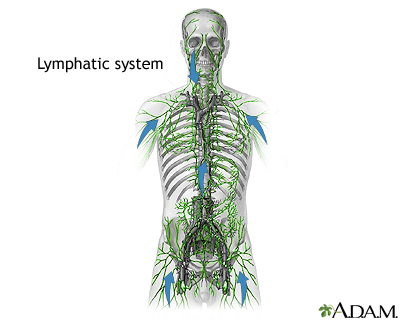

The lymph nodes are small glands that make white blood cells (lymphocytes), which fight infection. Lymph nodes may trap the germs that are causing an infection. Cancer can spread to lymph nodes.